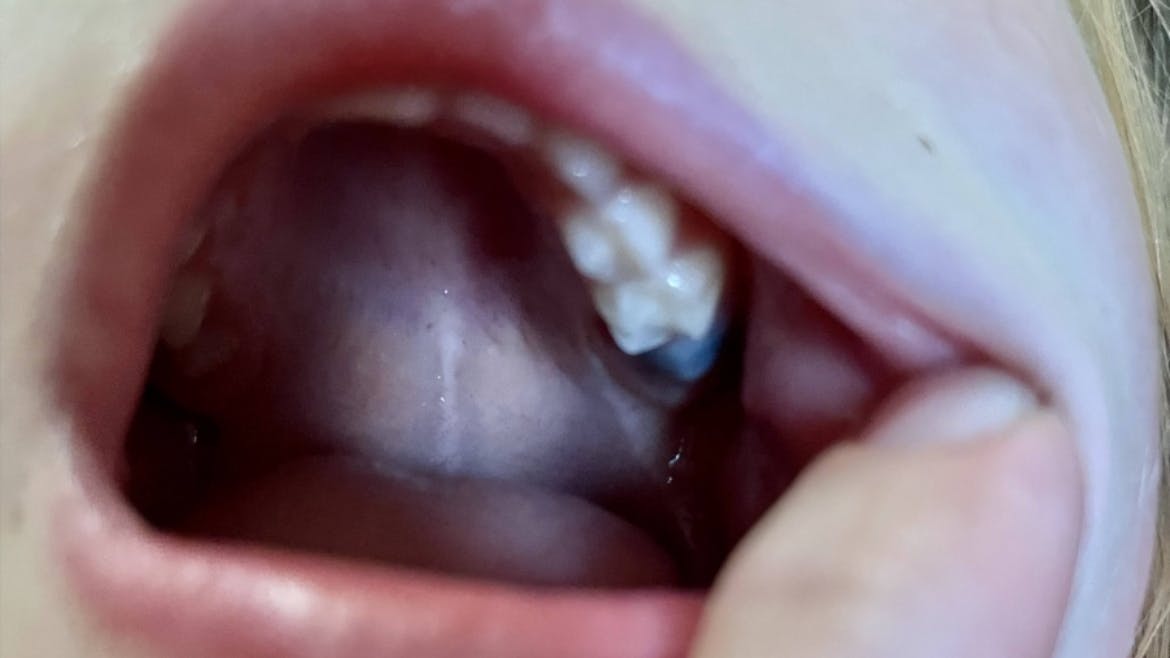

An EC often looks like a swollen blue to purple (or even black-covered) lump in the patient’s mouth.1,2 The cyst can be filled with clear liquid or blood.1 Unfortunately, parents, caregivers, and patients may become overly concerned when they suddenly notice this lump.